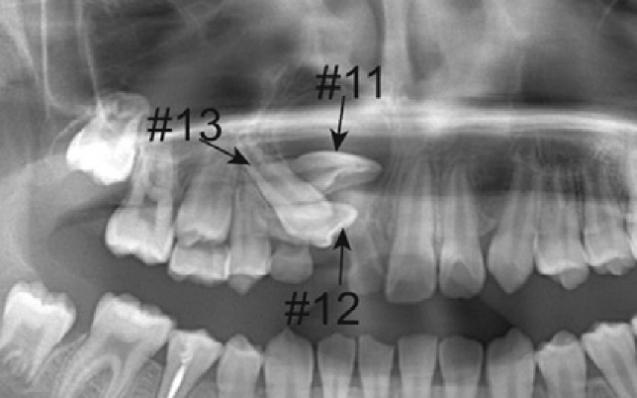

A 11-year-old girl came to our hospital complaining about “missing” front teeth. Radiographs showed that the right maxillary permanent canine, lateral and central incisors were all impacted. Particularly frustrating were the two closely stacked incisors with the roots excursing far away from the right position and embraced in a big cyst. If the incisors could not be drawn and aligned, the girl would have to face a front-teeth-missing adolescence with affected facial esthetics, oral function and self-confidence.

The orthodontic team made a delicate treatment plan after comprehensive examination and analyses. The three impacted teeth were under traction one by one, and the long-distance controlled root tipping was achieved with precise biomechanics. More importantly, a novel crimpable “gate spring”, invented by Prof. Yu Li and Prof. Zhihe Zhao, was used to boost the large-angle root torque movement with high efficiency, playing a pivotal role in perfection of this case.